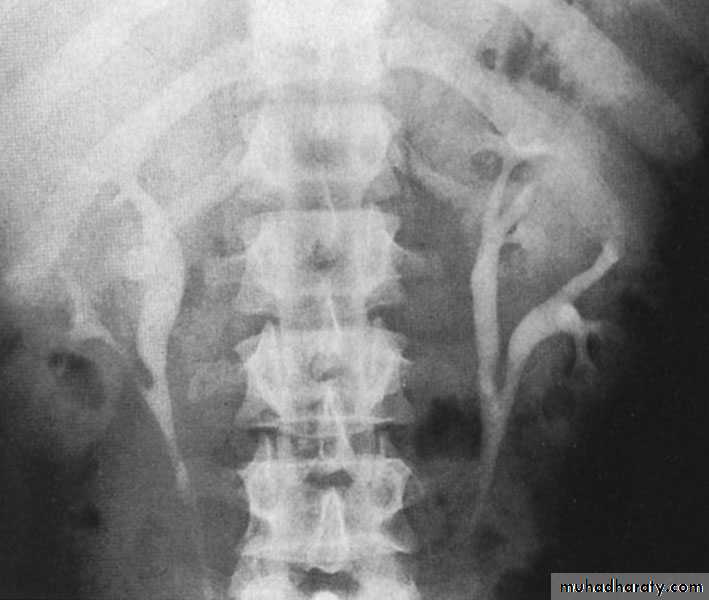

Ureteroceles

Is due to congenital atresia of the ureteric orifice which causes a cystic dilatation of the intramural portion of the ureter

Women > men

Sometimes involves with ectopic ureter

More prone to stone disease & UTIs

Clinical Features : Asymptomatic

Repeated UTIs, Hematuria

Diagnosis:

IVU, cystoscopy, cystogram

The ‘adder head’ on excretory urography is typical.

Treatment:

Asymptomatic : no treatment

Cystoscopy with diathermy cauterization of the hole

Nephrectomy in non functioning kidney

In complicated cases, ureteral reimplantation and vesical reconstruction

Cobra (Adder) head appearance of ureterocele